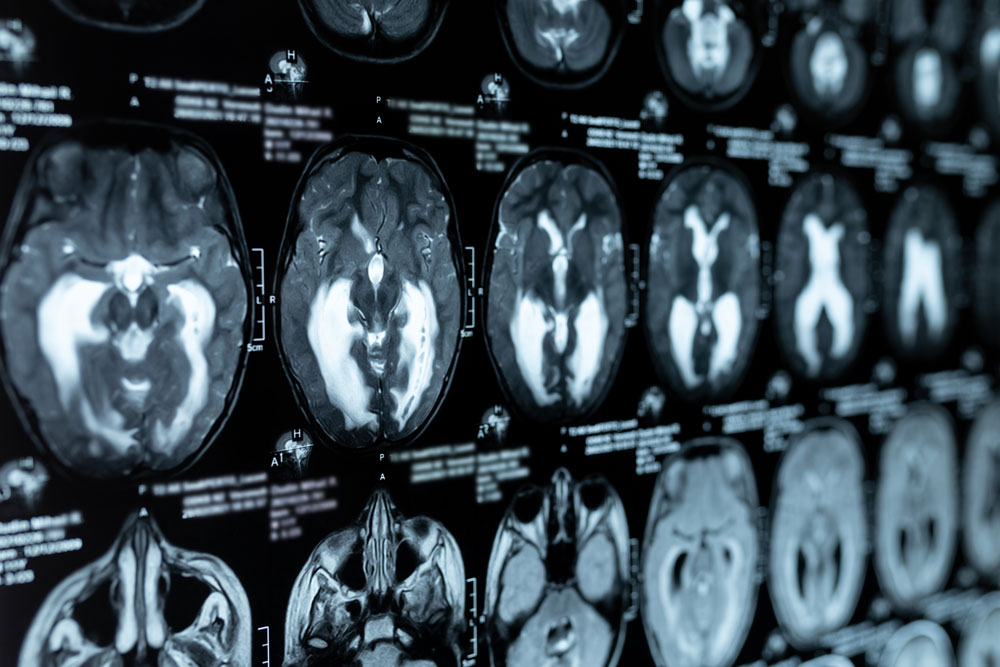

Magnetic Resonance Imaging (MRI) is a technique for capturing photographs within the body that uses powerful magnetic fields and radio waves. High-quality pictures of the interior of the body are recorded through a painless, non-invasive process called an MRI scan. MRI scans are frequently used to examine the joints, muscles, nerves, bone marrow, blood arteries, and other bodily systems.

- Head and Neck

- Neurology